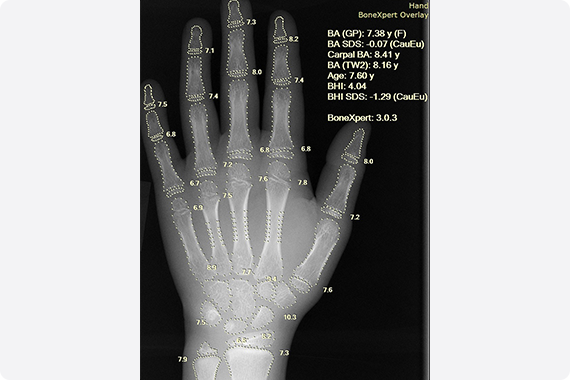

AI解析で、成長の“今”をより正確に

当院では、手首のレントゲン画像を BoneXpert(ボーンエキスパート) というAI解析システムで評価しています。従来は専門医が手作業で行っていた骨年齢の判定を、BoneXpertではAIが自動で解析するため、より精度の高い診断が可能です。日本国内での導入施設はまだ限られており、正確な骨成熟度の測定を行える点は当院の大きな強みです。成長のタイミングや将来の身長予測、ホルモン治療などの判断に役立てています。

BoneXpertの特長

ぶれの少ない客観評価

医師の手作業による読み取りの個人差を減らし、再現性の高い骨年齢を提示します。

短時間で結果をお伝え

撮影から解析までがスムーズ。外来での説明がよりわかりやすくなります。

将来身長の推定に対応

骨年齢・現在の身長・体重などの情報から予測最終身長を算出し、今後の見通しを丁寧にお伝えします。

骨の健康度の目安

骨の量や成熟度の指標(例:Bone Health Index等)も参考に、成長全体を総合評価します。